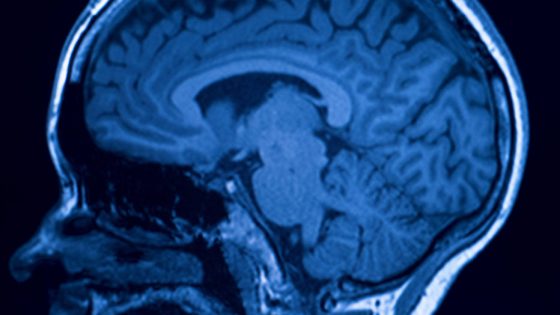

Nossas reações podem ser pré-definidas, mas não absolutas. Um cérebro tem muito para a nossa mente, algo que poderia ajudar e algo que poderia prejudicar –...